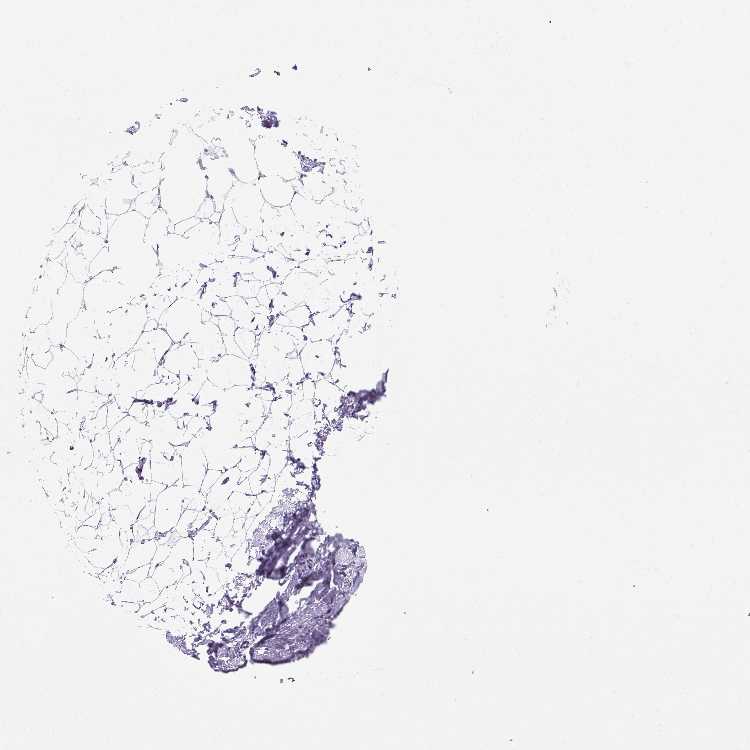

Information about each individual sample is listed below, including gender, age, a tissue section image and estimated fractions of cell types. nTPM (normalized transcripts per million) values give a quantification of the gene abundance which is comparable between different genes and samples.

Female, age 52

Breast sample 373

nTPM: 0.5

Cell types%

Glandular cells:

15

Adipocytes:

5

Other cell types:

80